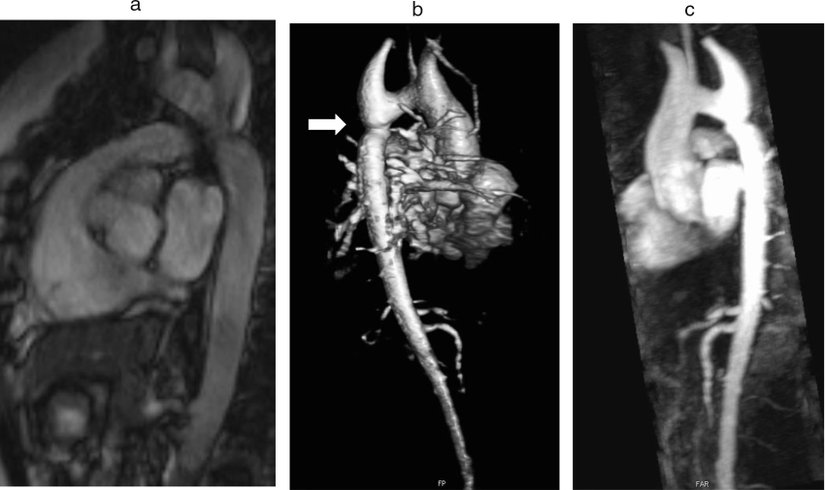

En yaygın konjenital kardiyovasküler malformasyon, Turner Sendromuna sahip hastalarının %20 ila %30'unda bulunan biküspit aorttur. Bununla birlikte, asemptomatik vasküler anormallikler yetişkinliğe kadar teşhis edilemediğinden prevalansını belirlemek zordur. Biküspit aort, sonraki aort dilatasyonu ve hatta aort diseksiyonu için zemin hazırlayıcı bir faktördür. Bu nedenle, Turner Sendromu ve biküspit aortu olan hastalar aort dilatasyonu geliştirmeye eğilimlidir ve yaşamları boyunca kardiyovasküler takibe ihtiyaç duyarlar.

İkinci en sık görülen konjenital malformasyon, hastaların %7-18'inde görülen aort koarktasyonudur. Tersine, yeni doğan bir kız çocuğunda aort koarktasyonu bulgusu, vakaların %12'sinde mevcut olduğu için Turner Sendromu tanısını gerektirmelidir.

/old/content_media/ec05a04f572ca518a78c860d94eddbe4.jpeg)

MR'da transvers aort uzamasının sık görülmesi aort koarktasyonuna eşdeğerdir. Aort kanalının yanındaki fibrotik süreç, aort çaprazı seviyesinde aort darlığına neden olur. Aort koarktasyonundan kaynaklanan sol ventrikül çıkışının ters akış fenomeni, hipertansiyon ve aort dilatasyonundan sorumludur.